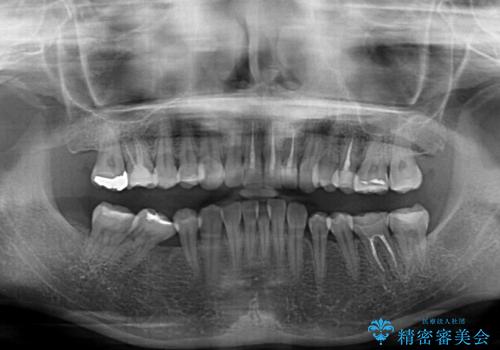

- 上下前歯のデコボコと奥歯の欠損を気にして来院された患者様です。

右下の欠損分は奥歯が倒れ込んでスペースがなくなっていたため、矯正治療により本来の位置に歯を移動させ、オールセラミックブリッジによる欠損補綴治療を行うこととしました。

全顎的にセラミッククラウンが多く装着されているため、インビザラインによる矯正治療を行うこととしました。